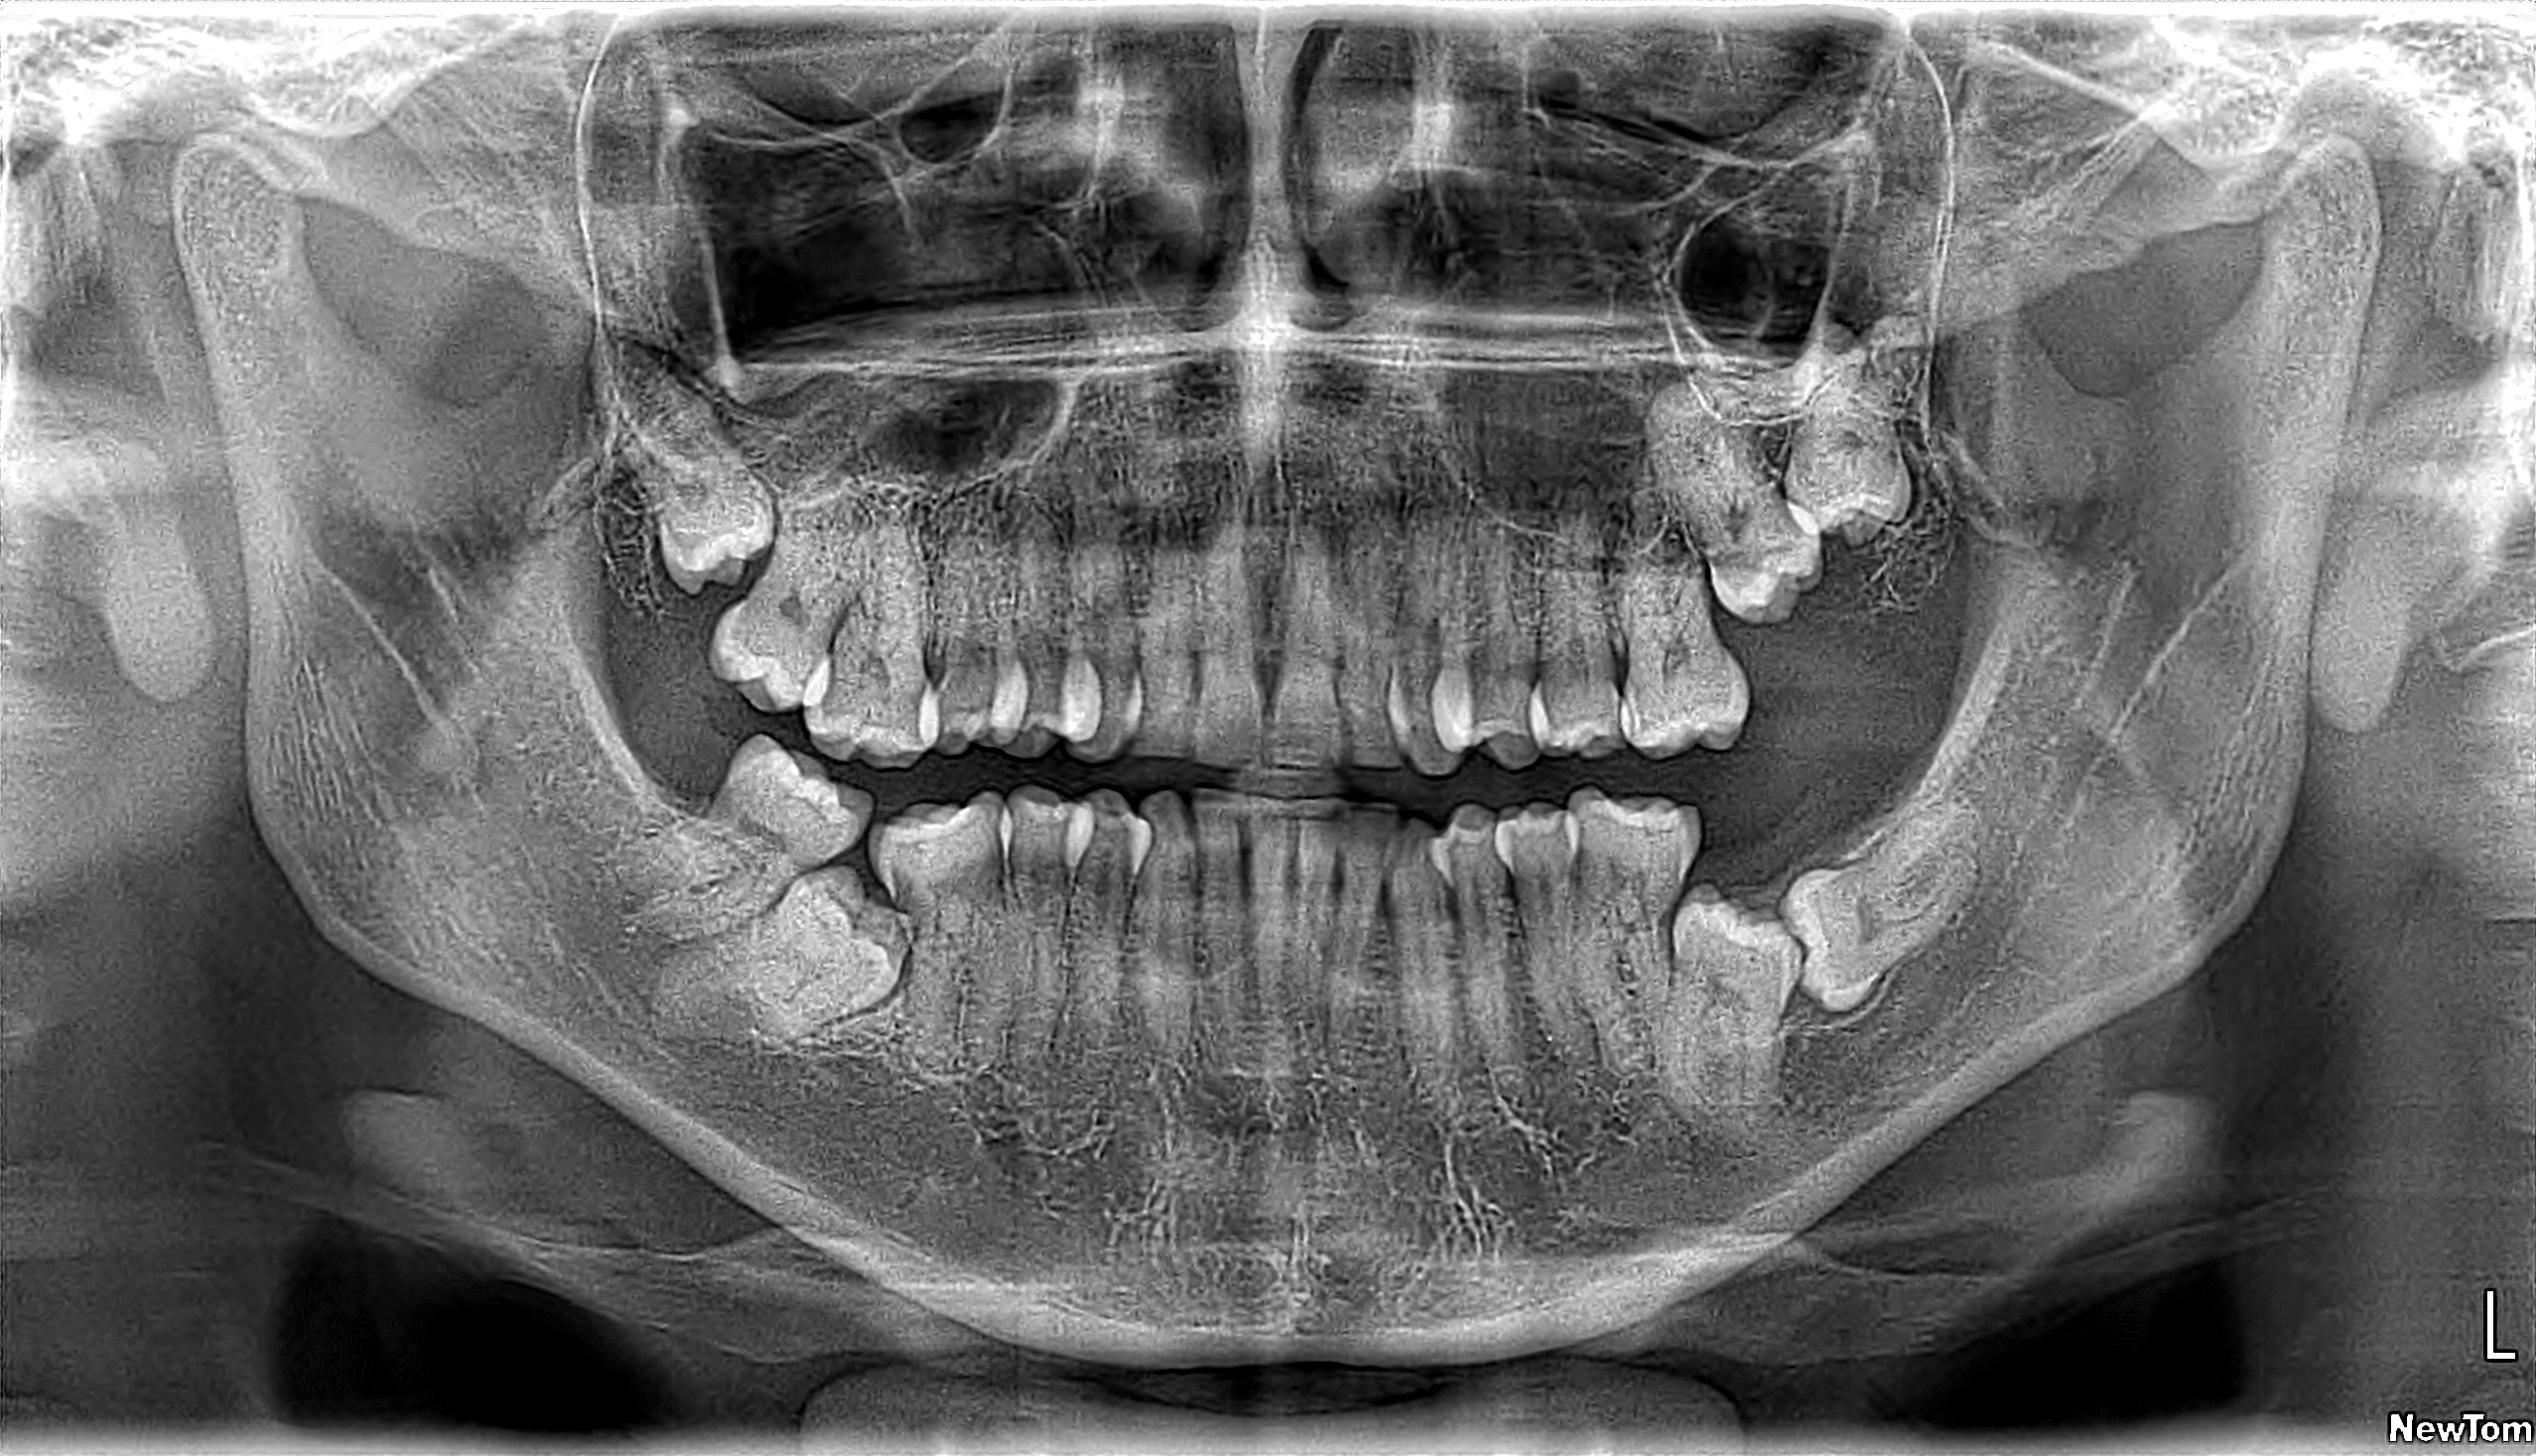

Radiografía Panorámica Dental

EXAMEN INTEGRAL

Radiografía Panorámica

Permite tener una visión general de todas las estructuras dentales y maxilofaciales en una imagen plana (2D), especial para evaluar evolución dentaria, patología de los maxilares e indispensable en ortodoncia.